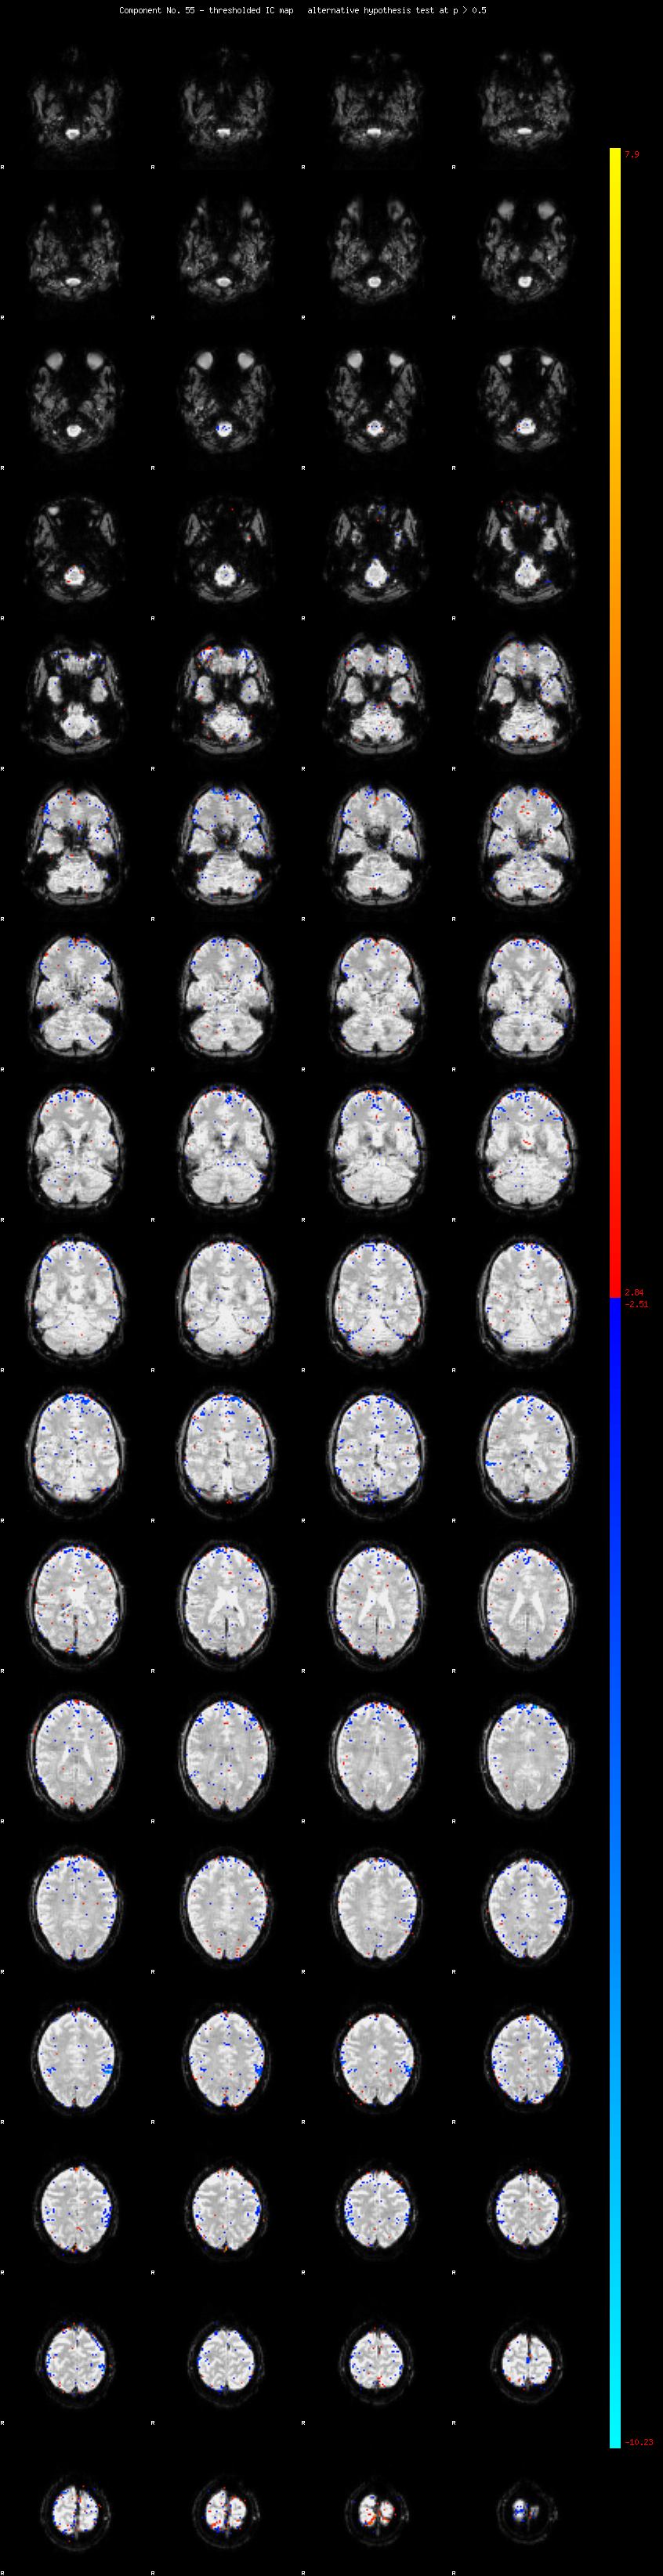

MELODIC Component 55

0.91 % of explained variance;     0.60 % of total variance